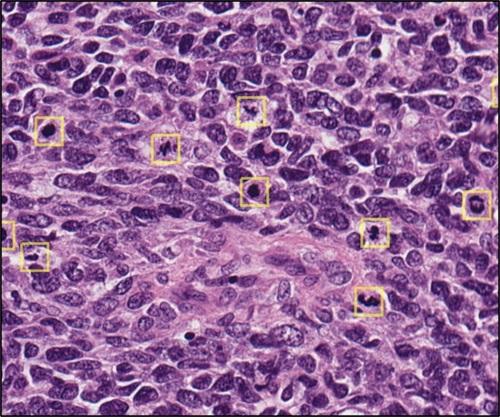

MitPro is an AI-driven solution that analyses H&E-stained tissue slides to identify mitotic figures, supporting faster mitosis counting and reducing variability across pathologists. It processes the entire slide, identifies the three highest-scoring hotspots, and allows verification of results. If desired, MitPro will also perform counting in manually defined hotspots.

MitPro is applicable to a range of samples from human cancers, including breast, lung, melanoma (including uveal melanoma), soft tissue sarcomas, leiomyoma, NETs, glioblastoma, meningioma, thyroid, and retinoblastoma.

MitPro enhances mitosis counting in H&E-stained images while fitting naturally into existing digital pathology workflows. Fully integrated with the Aperio HALO AP, MitPro brings AI-driven insights directly into routine practice - supporting pathologists with faster, more consistent, and reproducible results.

Soft tissue sarcoma example using hotspot 1